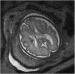

Abbildung 4: Pränatale Magnetresonanztomographie Fetus in der 32. SSW mit linksseitiger kongenitaler Zwerchfellhernie, koronale Schichtführung. Mit Hilfe der hier verwendeten Kontrastparameter können intrathorakal mit Mekonium gefüllten Darmanteile sehr hell dargestellt werden. Die Leber, sie ist etwas weniger hell als Mekonium, liegt intrabdominal. Am Hals ist auch die Glandula thyroidea zu erkennen. |

Abbildung 4: Pränatale Magnetresonanztomographie

Fetus in der 32. SSW mit linksseitiger kongenitaler Zwerchfellhernie, koronale Schichtführung. Mit Hilfe der hier verwendeten Kontrastparameter können intrathorakal mit Mekonium gefüllten Darmanteile sehr hell dargestellt werden. Die Leber, sie ist etwas weniger hell als Mekonium, liegt intrabdominal. Am Hals ist auch die Glandula thyroidea zu erkennen. |